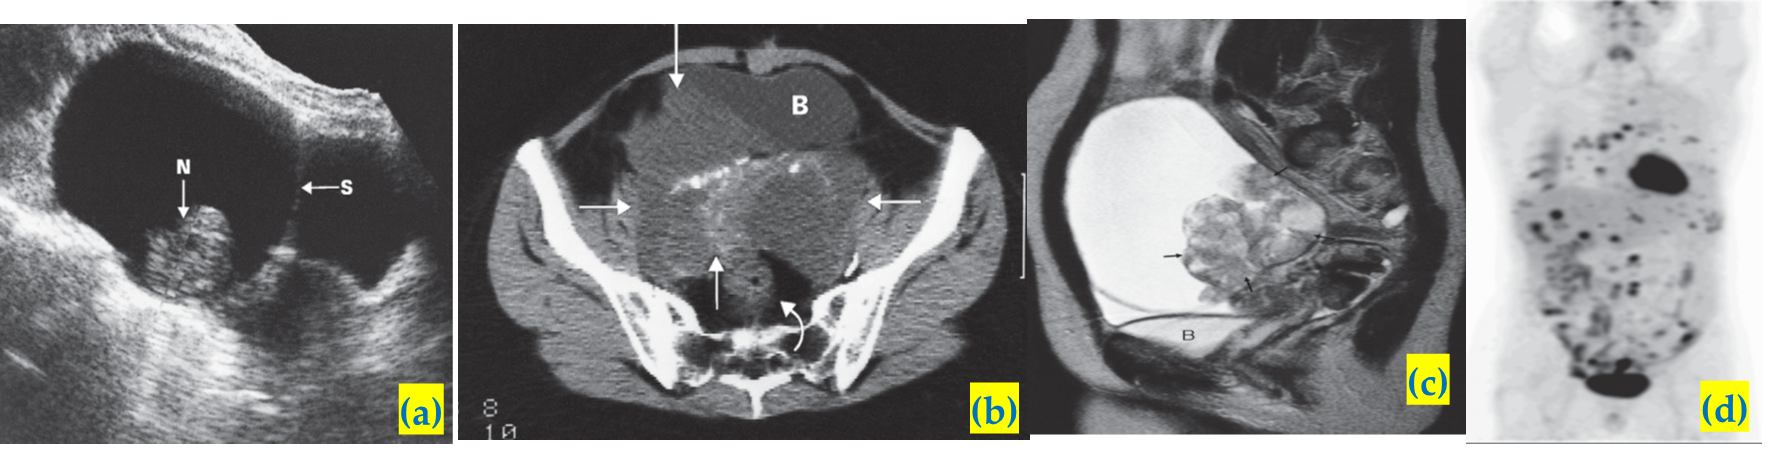

Ovarian carcinoma.

A) Longitudinal ultrasound scan showing a very large multilocular cystic tumour containing septa (S) and solid nodules (N). The lesion was a cystadenocarcinoma..

B) CT scan showing a large partly cystic, partly solid ovarian carcinoma (arrows). The tumour, which contains irregular areas of calcification, has invaded the right side of the bladder (B). The rectum is indicated by a curved arrow.

C) MRI scan showing a partly solid and partly cystic tumour. The cystic component is of high signal intensity on this T2-weighted image.

D) FDG-PET/CT in a patient with disseminated ovarian cancer. Abnormally increased activity is seen in the chest, liver and peritoneum. Normal cardiac and bladder activity is demonstrated